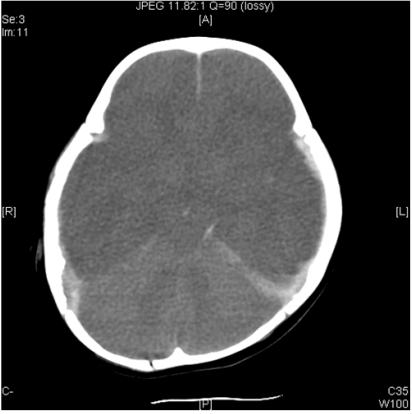

73. 一位 4個月大的嬰兒,因為意識障礙入院,GCS:E2V2M4,主訴昨天曾從40公分床墊滾下, 其頭顱外表無明顯傷痕或血腫,電腦斷層如圖,則下列何者為正確處置? (A)應插管使用呼吸器,將二氧化碳分壓維持在 20 mm Hg 以下以降低顱內壓 (B)查看眼底是否有視網膜出血 (C)考慮通報 115 專線 (D)應立即給予 midazolam 2 mg/kg/hr 以預防痙攣